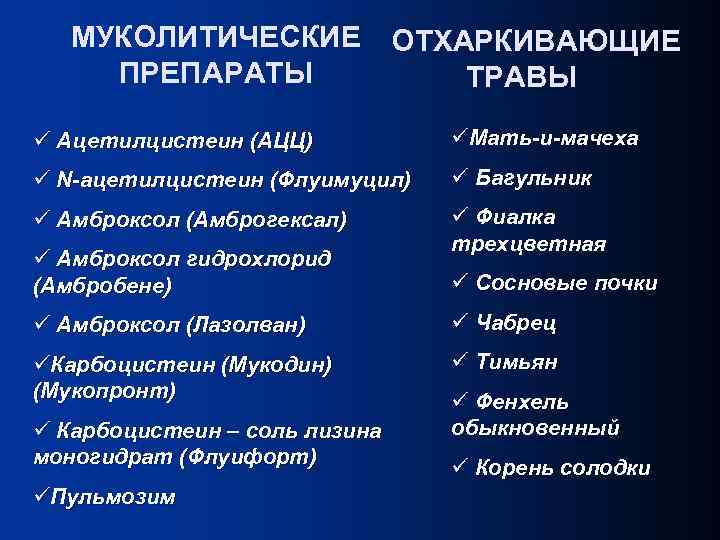

МУКОЛИТИЧЕСКИЕ ПРЕПАРАТЫ ОТХАРКИВАЮЩИЕ ТРАВЫ ü Ацетилцистеин (АЦЦ) üМать-и-мачеха ü N-ацетилцистеин (Флуимуцил) ü Багульник ü Амброксол (Амброгексал) ü Фиалка трехцветная ü Амброксол гидрохлорид (Амбробене) ü Сосновые почки ü Амброксол (Лазолван) ü Чабрец üКарбоцистеин (Мукодин) (Мукопронт) ü Тимьян ü Карбоцистеин – соль лизина моногидрат (Флуифорт) üПульмозим ü Фенхель обыкновенный ü Корень солодки